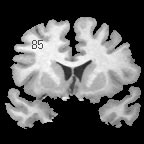

| + | |+ '''Fig 1. EM Segmentation: Cross-Sections of Segmentations (1993)''' | ||

| + | |valign="top"|[[Image:one.jpg|thumb|252px|slice of T1 weighted mr (right temporal lobe has bad "shading")]] | ||

| + | |valign="top"|[[Image:two.jpg|thumb|252px|threshoding result]] | ||

| + | |valign="top"|[[Image:three.jpg|thumb|252px|EM result]] | ||

| + | |} | ||

The EM segmenter grew out of a collaboration between Sandy Wells, Ron Kikinis and Martha Shenton in about 1993. The goal was to get good automatic segmentations of white matter and gray matter from T1 weighted MRI. The biggest difficulty was the intensity inhomogeneities, or "shading", artifact in the images that was due to the MRI scanner used for research at that time. The effect of the artifact was that a single threshold could not be used to separate white matter and gray matter.

Various approaches to the problem were tried, some giving good results, but there were remaining imperfections in the results. Eventually, we decided to construct an explicit representation of the intensity artifact, and attempt to recover the artifact and the segmentation simultaneously.

We chose the Expectation Maximization (EM) algorithm, a statistical estimation method that is used when some data is considered to be "missing". The result was an iterative algorithm that alternates between two steps.

In the "E" step, the probability of the tissue label at each voxel is estimated, given the image data and the current estimate of the intensity artifact.

In the "M" step, the intensity artifact is re-estimated, given the image data and current estimate of the tissue label probabilities.

The EM segmenter proved to be very robust to shading artifacts, but in addition, it was also robust to "inter-scan inhomogeneities". With previous classification approaches to segmentation, "training" was needed on a per-scan basis, because of intensity changes from scan to scan.

The EM segmener was the first algorithm that could produce high quality segmentations of white matter and gray matter from MRI, with no manual intervention needed on a per case basis. This proved to be very valuable in a large longitudinal study of MS in the period 1994 - 1995.